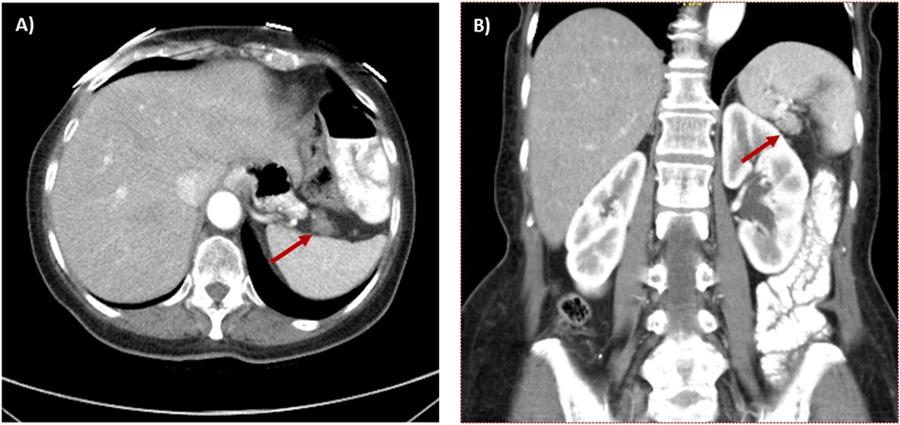

Figure 1. Abdominal CT Scan Demonstrating Recurrent Left Upper Quadrant Mass at Splenic Hilum. Published with Permission

A) Axial CT image with arrow noting left upper quadrant mass that was PET-avid; and B) coronal CT image with arrow identifying same left upper quadrant mass.